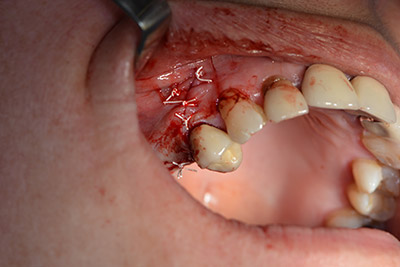

An absorbable membrane was used as the barrier in the buccal direction and covered the augmentation. Finally, saliva-proof sutures were placed (Fig. 15 to 19).

Augmentation with autologous bone

Image 15

Image 16

Implantation

Image 17

Implantology

Image 18

saliva-proof wound closure

Image 19